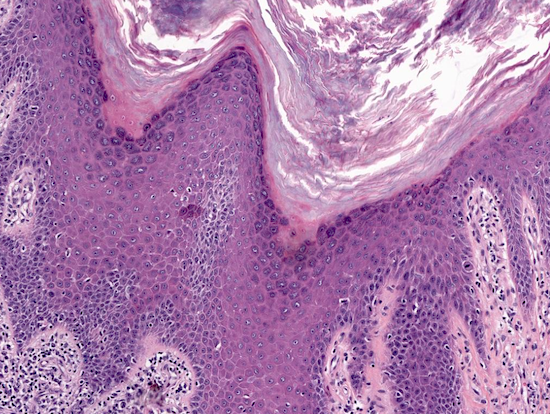

What is abnormal about the epithelium of these tissues, and what may that indicate with regards to malignancy?

A

Epithelial dysplasia.

Does not necessarily indicate cancer, however they can develop into cancer.